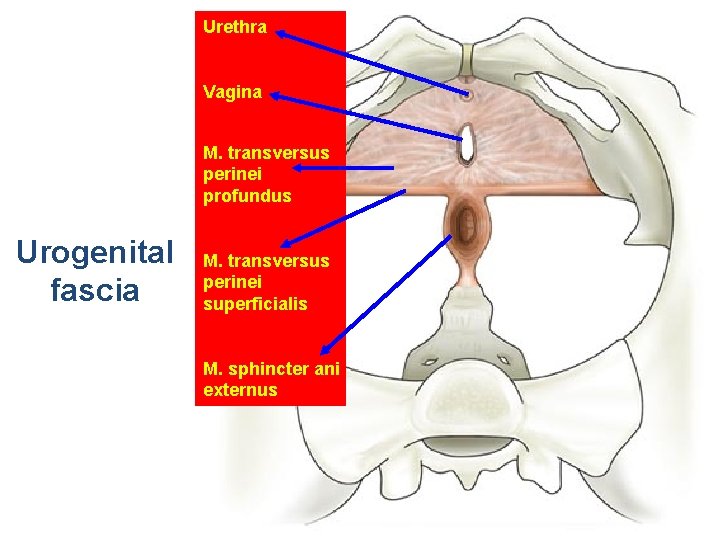

Urethra Vagina M. transversus perinei profundus Urogenital fascia M. transversus perinei superficialis M. sphincter ani externus

Layers of the Anterior Triangle of the Perineum • Skin • Subcutaneous tissue . Camper's fascia . Colles fascia • Superficial space . Clitoris and its crura . Ischiocavernous muscle . Vestibular bulb . Bulbocavernous muscle . Greater vestibular gland . Superficial transverse perineal muscle • Deep space-perineal membrane . Compressor urethrae . Urethrovaginal sphincter

• Ürogenital trigon: – – M. Transversus perinei superficialis M. İschiocavernosus M. Bulbocavernosus M. Transversus perinei profundus • Anal trigon: – M. Levator ani – M. Sphincter ani externus